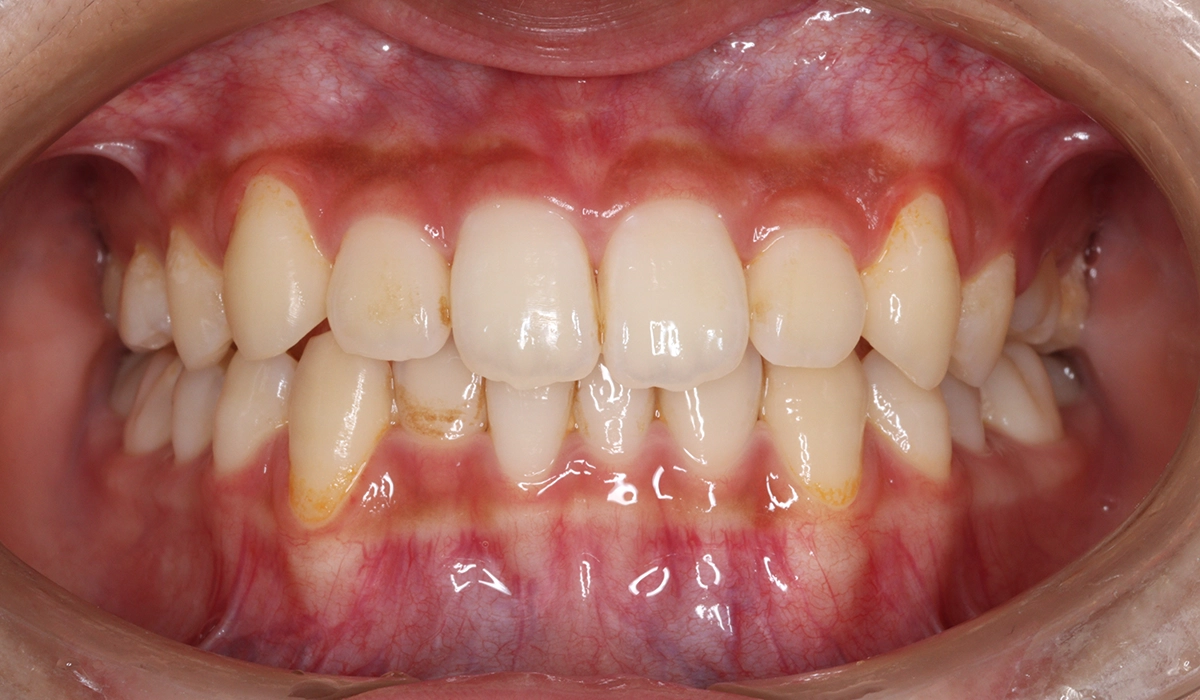

術前:正面